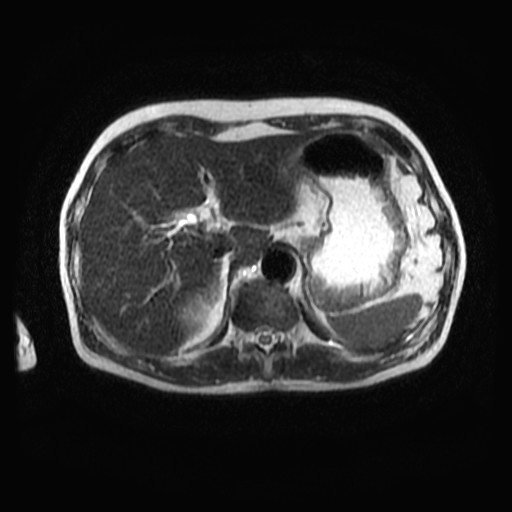

Mri t1 t2 腹部. Mriはctと違いx線を使わないため放射線被ばくになることはありません。 mri画像の色の違いとは? mriもct同様に白と黒で画像表示されます。 mriでよく使うのがt1画像とt2画像です。 t1とt2の見え方については表をご覧ください。 t1画像. 現在、当クリニックでは上腹部MRI検査として、横断像を4シーケンス<T1(in、 out Phase)T2 HeavyT2 DWI>、冠状断を1シーケンス<HeavyT2>を撮影ルーチンとしております。スライス厚は5mmを基本として35枚程度の撮影です。. Open MRIの高い性能を感じ取ることができる。 (1) 基本的シーケンス Open MRIでは、MRI検査に必要な基本シーケンスを撮像 することができる。具体的にはT1強調画像、T2強調画像、プ ロトン密度強調画像、T2*強調画像、MRAngiographyなど である。.

あえずt1, t2とtr, teとの関係を、ざっくりと理解することを目標にしています。 ※t1とt2は組織のパラメータで、trとteは撮影装置のパラメータ(機械で調整する 値)になります。エックス線検査がラジオならmriはテレビに相当します。ラジオは選局. Mri検査を行うための必須条件 1) 本品による治療法に習熟し、 製造販売業者が提供する研修 を修了した医師(以下、本治療法施行医師)が、事前に当該患者のmri検査の安全性を確認すること。 2) 本治療法施行医師は、患者に対して、mri検査を実施する医師及び技師に植込み患者手帳等(mri検査の. (t2強調画像) 頚椎(t1強調画像) 骨盤(t2強調画像) 膝関節(プロトン密度強調画像) 腹部(t2強調画像) 腹部(t1.

腹部mri検査 消化器系の検査 看護roo カンゴルー

腹部mri検査 消化器系の検査 看護roo カンゴルー